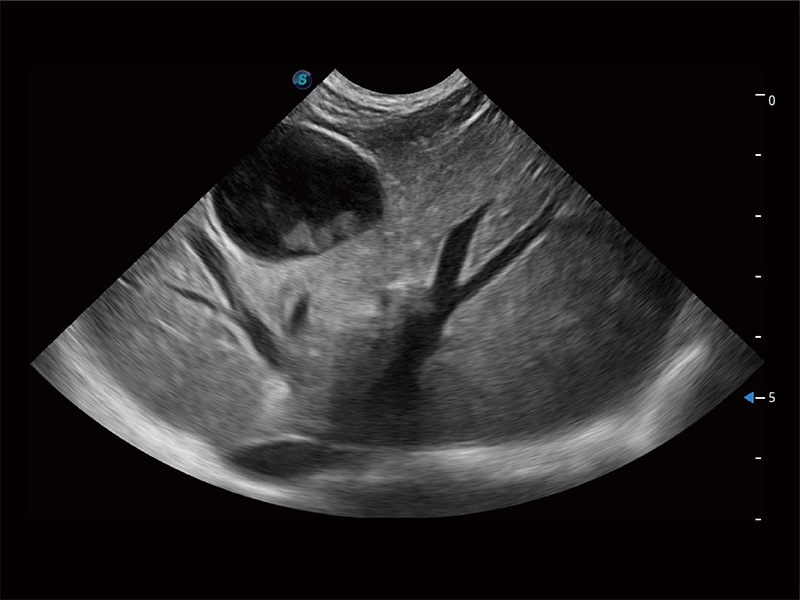

ProPet 80 配備了豐富的心臟探頭群、先進的成像技術(shù)和專業(yè)的心臟測量工具,可幫助動物醫(yī)生為不同體型和生理結(jié)構(gòu)的動物提供心臟和心肌功能的全面評估。